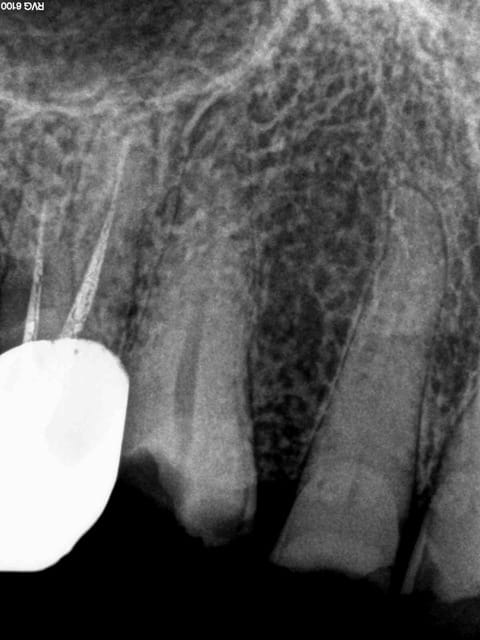

Et 2 autres pour terminer la journée. Ca fait 5 endos molaires aujourd'hui.

Pas trouvé de MV2 sur la 7.